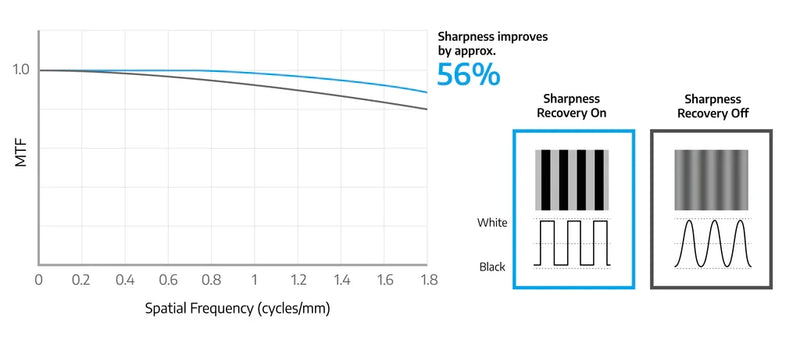

Μια ιατρική παρακολούθηση πρέπει να είναι σε θέση να είναι υψηλή φωτεινότητα για να ανταποκριθεί στα πρότυπα απόδοσης. Ωστόσο, για να επιτευχθεί υψηλή φωτεινότητα σε έναν πίνακα LCD, πρέπει να αυξηθεί η αναλογία ανοίγματος εικονοστοιχείων. Αυτό προκαλεί μια τυπικά αναπόφευκτη μείωση της ευκρίνειας. Με την μοναδική τεχνολογία ανάκτησης της ευκρίνειας του Eizo, αποκαθίσταται η μείωση της ευκρίνειας (MTF). Αυτό σας επιτρέπει να εμφανίζετε μια εικόνα με ασφάλεια στην οθόνη που ισχύει για τα δεδομένα πηγής, ακόμη και σε υψηλά επίπεδα φωτεινότητας.

Το MTF μετράει αριθμητικά πόσο πιστά ο πίνακας μεταφέρει λεπτομερώς από τα αρχικά δεδομένα εικόνας για προβολή. Όταν η ανάκτηση της ευκρίνειας είναι ενεργοποιημένη, στην περίπτωση ζεύγους γραμμής 2 pixel (χωρική συχνότητα 1,609 κύκλων/mm), το MTF αυξάνεται κατά περίπου 56%.